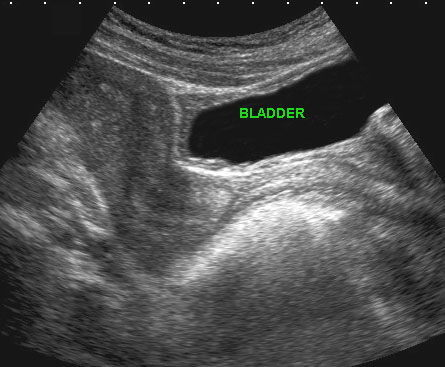

Bệnh nhân nữ 45 tuổi với tiền sử đau khi tiểu tiện kéo dài. Nội soi bàng quang âm tính.

CT cho thấy một khối dạng mảng bám, bờ không đều (mũi tên).

TVUS xác nhận một ổ lạc nội mạc tử cung lớn (mũi tên) trong khoang trước bàng quang (khoang Retzius). Lưu ý bờ không rõ với tử cung.